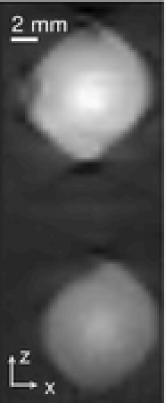

A phantom was built that contained transparent gelatin shaped in a cylinder of radius mm and height mm, as shown in Fig. 4. Embedded in the phantom were two plastisol spheres of mm diameter. The right sphere shown in Fig. 4 possessed a larger absorbing coefficient at the illumination wavelength of nm. Additionally, on one end of the cylinder an acrylic hollow cylinder was embedded about mm deep in order to attach the phantom to the rotational motor. During the scanning, both the phantom and the transducer array were oriented vertically, i.e., parallel to the z-axis in the coordinate system shown in Fig. 3. The transducer array was fixed while the phantom was rotated about the z-axis over with a step size of , resulting in a partially covered spherical measurement surface. At each transducer location, temporal samples were acquired for two consecutive illuminations and then averaged together, improving the signal-to-noise ratio. Accordingly, the dimension of the measured data set was . Note that the data acquired by the first element on the 64-element transducer array were employed for time alignment intead of for image reconstruction. We repeated the data acquisition procedure described above times, creating an ensemble of noisy measurements.

Images were reconstructed by first solving the penalized least-squares objectives defined by Eqns. (16), (17) and (18), where the system matrices and were calculated on the fly [22]. The phantom was contained in a volume of dimension mm3. For the reconstructions, the expansion functions were chosen to be distributed on a SC grid of spacing mm and distributed on a BCC grid of spacing mm, respectively. For the KB function-based imaging model, we let , , and in Eqn. (9) [39]. Accordingly, and were of dimension -by- and -by-, respectively (thus and ). The values of and were chosen so that the size of the reconstructed volume approximately matched the size of the original experimental volume. From the estimated coefficient vectors and , and were determined by use of Eqns. (19) and (20).